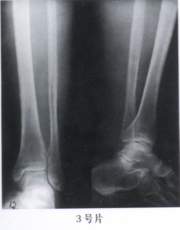

3.(3号片)

A、正常胫腓骨X线片

B、胫骨下段骨折

C、腓骨下段骨折

D、胫腓骨双骨折

E、踝关节脱位

答案:1—6:EDACAC 15—20:ACBDED